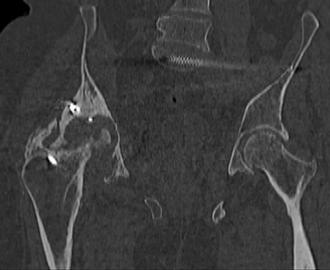

Пациент 49 лет, паровозная травма 23.2.2006, получил вертикальная нестабильное повреждение таза, разрыв левого крестцово-подвздошного сочленения, перелом лонной, седалищной костей слева, T-образный оскольчатый перелом правой вертлужной впадины с переломом заднего края, вывих правого бедра, посттравматическая пояснично-крестцовая плексопатия с обеих сторон, паралич мышц правой голени.

В день травмы - вправление вывиха, скелетное вытяжение, 14.3.2006 чрескостный остеосинтез таза. 20.4.2006 остеосинтез правой вертлужной впадины пластинами, осложнившийся нагноением межмышечной гематомы правой ягодичной области. Получал консервативное лечение, было достигнуто полное заживление раны. 24.7.2006 введены илиосакральные винты слева. С декабря 2006 года и по настоящее время ходит на костылях без опоры на правую ногу. Планируется THA. Помогите определиться с вариантом костной пластики? И какую укрепляющую конструкцию использовать?